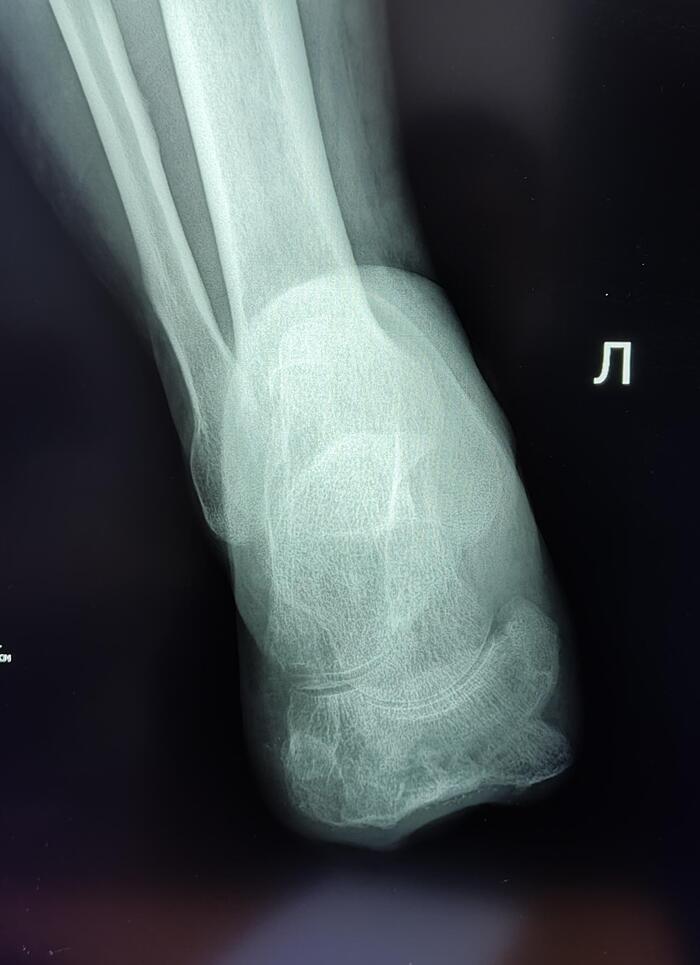

В общей сложности пострадавшая от обморожения провела в больнице 49 дней. Периодически даже впадала в кому. Но это мелочи по сравнению с возможными в таких ситуациях последствиями. Ведь при длительном воздействии низких температур замедляется кровоток. Ткани и органы испытывают кислородное голодание. Потеря пальцев, носа, ушей в таких ситуациях – обычное дело. А в более серьёзных случаях всё заканчивается ампутацией конечностей.